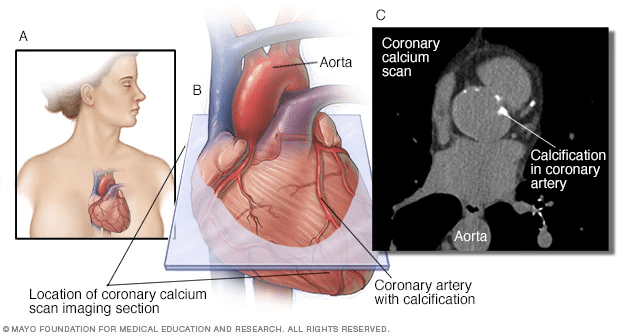

Coronary Artery Calcium Scoring Current Status And Future Directions

Coronary Artery Calcium Scoring: Its Practicality And Clinical Utility

calcium coronary artery scoring significant cardiovascular clinical practicality ccjm

calcium coronary artery calcification plaque amount scanner

Coronary Artery Calcium Scoring - A Risk Predictor

Coronary Artery Calcium Scoring

calcium coronary artery scoring screening heart disease

Coronary Artery Calcium Scoring — Is It Useful? - Dr Ross Walker

Calcium Score / CT Heart Scan

calcium coronary atherosclerosis arteriosclerosis ct arteries treatment diagnosis cardiology

Coronary Calcium Score - Capital Heart Centre

CT Calcium Score Scan | Perth Radiological Clinic

calcium score coronary